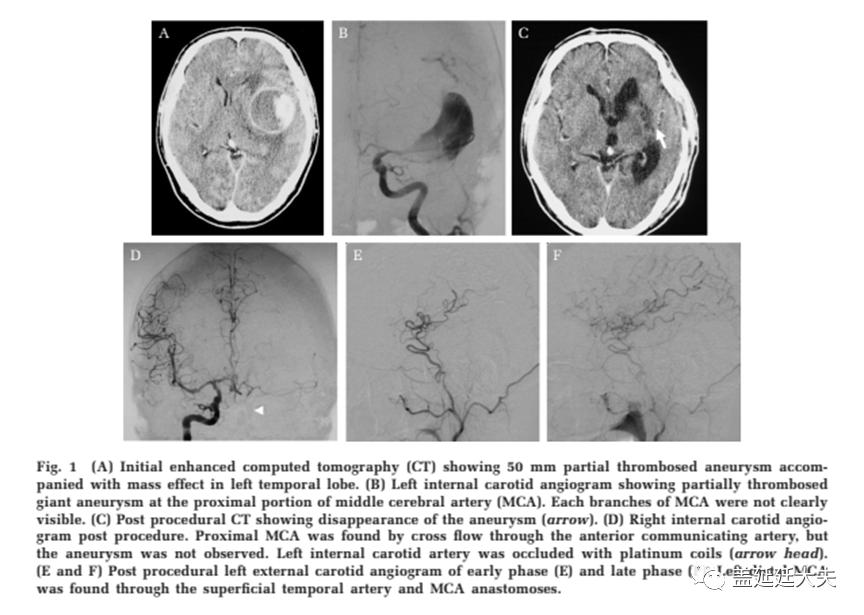

感染性颅内动脉瘤(IIAs) 占所有脑动脉瘤的0.7–5.4% ,被证实继发于症状性的细菌感染,尤其是感染性心内膜炎,偶尔也存在真菌及分歧杆菌的感染。约3-10%的感染性心内膜炎(IE)患者可检查出动脉瘤,远期病情可进展,炎症性栓子脱落导致颅内动脉远端栓塞。对于这些未破裂动脉瘤,采取抗菌治疗可缓解或者缩小其体积。相反地,破裂的,有症状的或正在生长的动脉瘤应该考虑手术或血管内介入治疗。血管内介入治疗变得更受欢迎,并已被采用作为治疗指南。新泻大学神经外科 2002年至2018年就收治的3例IIAs病人进行讨论。包括2男1女,总共6个动脉瘤。平均年龄43.3岁。1例患者最初表现为实质内出血,1例有占位效应,另1例有4个IIAs(1个引起蛛网膜下腔出血(SAH),3个引起迟发性脑实质出血)。所有动脉瘤的直径平均大小为12.2毫米,动脉瘤优先位于大脑后动脉远端以及大脑中动脉。在病例2中, IIA位于大脑中动脉近端。3例为梭状动脉瘤,3例为囊性动脉瘤。所有病例均继发于IE。其中一例致病菌为粪链球菌,一例为唾液链球菌。第三例中的病原体未发现。

5个动脉瘤应用弹簧圈结合NBCA进行栓塞。另1个动脉瘤采用血管内介入结合手术(病例2)。在血管内治疗组,2例使用弹簧圈进行近端血管闭塞,3例使用弹簧圈孤立动脉瘤,1例使用弹簧圈结合NBCA栓塞动脉瘤。除病例2外,所有IIAs均在发现后24小时后治疗。所有患者都有良好的临床结果,无并发症,无动脉瘤复发或再出血。感染性颅内动脉瘤很少见,血管造影上典型的表现是涉及颅内大动脉二、三级分支,多发不规则或梭形的动脉瘤。IIAs通常直径小,但可以迅速扩大。Alawieh等人报告了44.2% IIAs直径<5mm, 少数非典型的病例可出现巨大动脉瘤。56.9%位于MCA, 13.1%位于PCA。我们推测,无症状动脉瘤的动脉内壁可能已经存在一个脓肿,引起炎症和脓囊进展,导致形成巨大的动脉瘤造成占位效应。IIAs可能无法检测到,随着 IE发病至IIA破裂可能持续2 - 5周。感染性心内膜炎(IE)患者必须密切监测一系列神经影像,包括MRA,CTA,特别是发病后2-5周。尽管非侵入性神经成像技术有了进步,但DSA仍然是黄金标准。如果非侵入性检查呈阴性,仍推荐行DSA脑血管造影。

IIAs的治疗策略是有争议的;选择包括保守的抗生素和影像随访,外科治疗或血管内治疗。抗生素治疗的感染性病因最多通常是细菌,有时是真菌,病毒,还有寄生虫,是标准的治疗方法。除非较大,症状性或扩张性未破裂的动脉瘤可以用抗生素治疗,并通过连续的神经成像进行监测。Matsubara报道了7例相关抗生素治疗病例,动脉瘤均消失,无复发或再出血。但也有研究表明,不能单纯使用抗生素来控制动脉瘤的生长。然而,在破裂的情况下,手术或血管内介入治疗应该被考虑,因为破裂的风险很高,死亡率为30%至80%。处理尤其具有挑战性, 其载瘤动脉血管壁脆性明显高于常规囊性动脉瘤。受影响的载瘤动脉和动脉瘤壁使开颅夹闭手术难度上升,甚至无法进行夹闭。但是当动脉瘤破裂伴有大的脑实质内血肿引起占位效应,则需要手术治疗。此外,一些IIAs因炎症广泛播散形成于近端脑动脉,因为他们的解剖位置,动脉瘤颈夹闭可能不太实际,所以需要行近端载瘤动脉闭塞或血管重建术覆盖远端血流。Ota等报道2例大脑中动脉远端动脉瘤破裂,通过动脉瘤孤立和血管重建成功治愈。